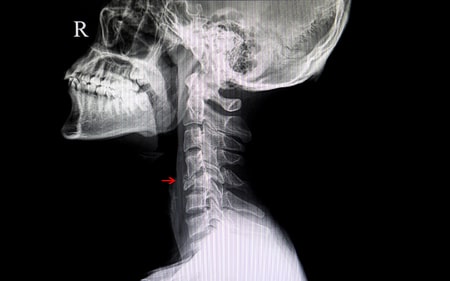

Radiografía

La radiografía es útil para valorar el grado de degeneración, observaremos si el disco intervertebral ha perdido altura, si las articulaciones facetarias tienen artrosis, en el caso de que la causa del dolor sea traumática podremos valorar fracturas y luxaciones.